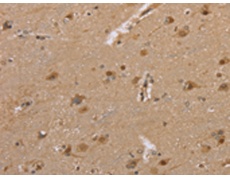

IHC positive control: |

Human brain and Human prostate cancer |

IHC Recommend dilution: |

50-200 |